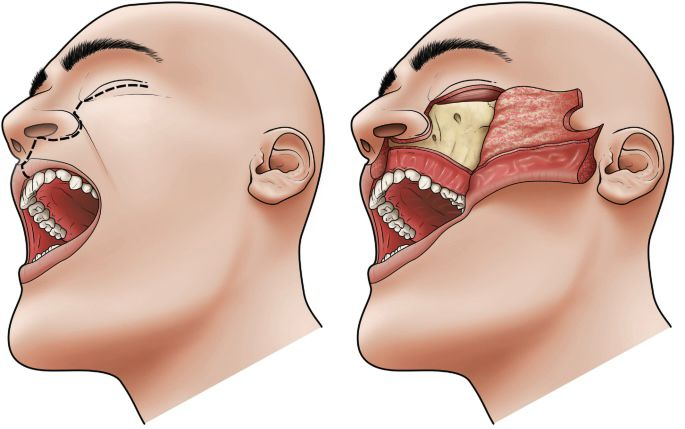

Maxillofacial & Oral Cancer

Maxillofacial &Oral Cancer

Tooth, Gum & Jaw Cancer Treatment

Fractured Jaw & Facial Bone Treatment